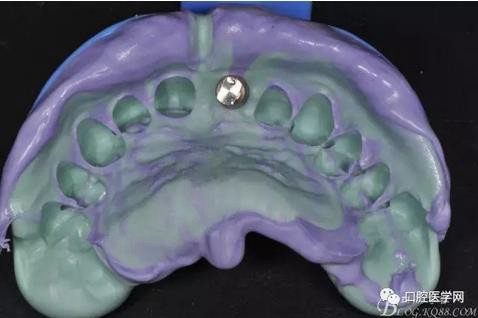

圖11 置閉口印模帽取模

圖12 硅橡膠取模